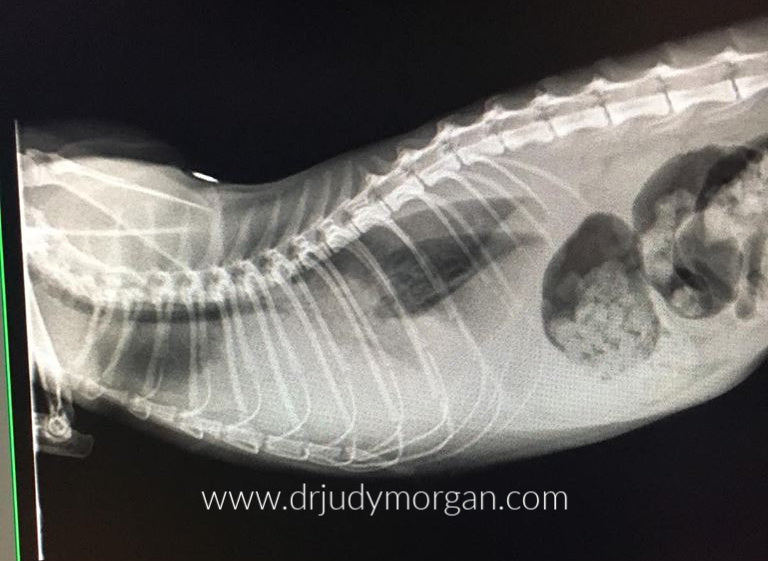

While the cardiologists are seeing this disease more often in dogs, they are not claiming the same issues for cats. However, this week I saw a four-year-old cat with dilated cardiomyopathy. The cat was eating a grain-free food. Cat food has been supplemented with taurine for years, as it is an essential amino acid for cats. Is there a connection here?